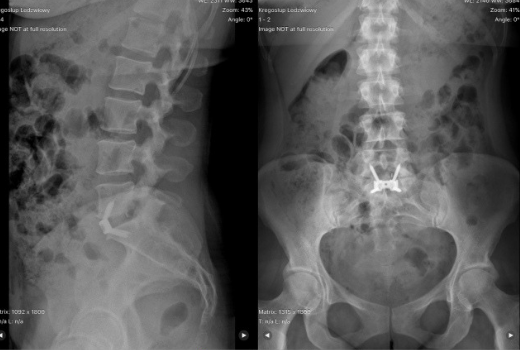

Czyli przednia lędźwiowa stabilizacja międzytrzonowa. Metoda polega na dojściu zaotrzewnowym do kręgosłupa i w przypadku leczenia odcinków kręgosłupa na poziomie dysków L4-L5 i L5-S1 odnotowuje bardzo dobre wyniki kliniczne. Obecnie operacje kręgosłupa wykonuje się najczęściej z dostępu tylnego. Jednak w przypadku odcinka kręgosłupa L5-S1 z dużym obniżeniem krążka najlepszym wyborem jest metoda ALIF. Dojście do tego miejsca za pomocą innej metody utrudnia talerz biodrowy lub konieczne jest preparowanie worka oponowego i korzeni nerwowych. ALIF tworzy doskonałe warunki, gdyż pozycja leżąca na plecach otwiera dostęp do miejsca zmienionego chorobowo.

Metodę ALIF wykorzystujemy m.in. do leczenia dyskopatii odcinka lędźwiowego na poziomach L4-L5 i L5-S1 przy wszczepieniu nieruchomych i ruchomych protez krążków międzykręgowych.

Zdecydowanym wskazaniem do jej zastosowania jest całkowite uszkodzenie krążka kręgowego oznaczające potrzebę zastąpienia go w całości implantem. Mocno uszkodzony krążek nieprawidłowo bowiem przenosi obciążenie w osi ciała i jest przyczyną dużego cierpienia pacjenta. W przypadku osób bardzo otyłych, z zaburzeniami osi ciała na wielu płaszczyznach lub ze skoliozą lekarz zawsze będzie rozważał wykorzystanie innych metod operacyjnych. Decyzja będzie za każdym razem podejmowana na podstawie indywidualnej diagnozy pacjenta – wyjaśnia dr Jurij Kseniuk.

ALIF daje bardzo dobre wyniki kliniczne przy odpowiedniej kwalifikacji w porównaniu z innym metodami, ponieważ nie pozostawia blizny w kanale kręgowym, nie wymaga bezpośredniego preparowania korzeni nerwowych i worka oponowego, zachowuje mięśnie przykręgosłupowe, zapewnia proste i swobodne dojście do dysku i odnotowuje największy procent osiągniecia zrostu kostnego. Oznacza to, że przypadki pacjentów leczonych metodą ALIF statystycznie najrzadziej wymagają reoperacji.

Duża powierzchnia implantu, przylegająca do sąsiednich trzonów niemal gwarantuje prawidłowe wgojenie, czyli zintegrowanie się implantu z tkanką kostną.